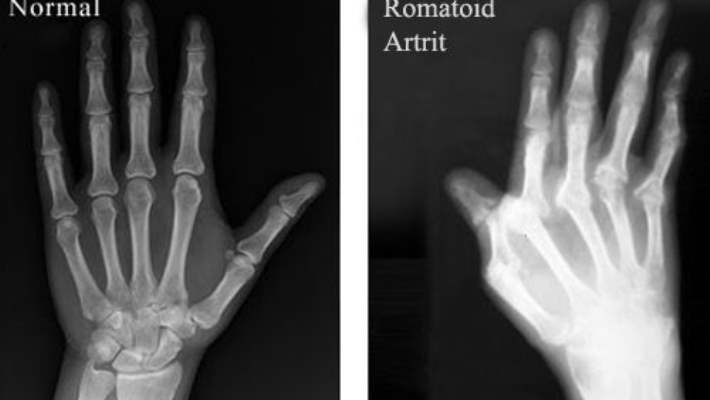

Romatoid artrit şişme, tutukluk, eklem tahribatı ve sakatlığa neden olan ağrılı bir iltihaplanmadır. Bu otoimmün (bağışıklık sistemine ait) bir hastalıktır ve hücreler üzerinde, eklemleri kaplayan ve yağlandıran bir etkiye sahiptir.

Kemik erimesi, el veya parmak iltihaplanmasında olduğu gibi sadece tek bir eklemi etkiler. Buna karşın, romatoid artrit genellikle simetrik olarak meydana gelir. Örneğin her iki bileği, her iki eli ve her iki ayak bileğini ve ayağı birden etkiler.